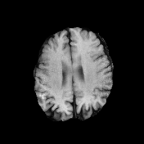

Brats MRI T1 Scans, FLAIR, Tumors. Lastly, we used a dataset of brain MRI scans [28] with two modalities: T1 (naive) and FLAIR (T2 Fluid Attenuated Inversion Recovery) [15]. We adapt the protocol that Cohen et al. [9] used for the Brats2013 datasets [27] to the more recent Brats2018 [3] dataset by varying the percentage of scans with tumors in the target domain. We selected transverse slices from the to range in the caudocranial direction [1] for both T1 and FLAIR scans. Each scan was classified as tumorous if more than of its pixels were labeled as such, and as healthy if it contained no tumor pixels. The training set contains images from each modality, with all source images (T1) being healthy and the target domain (FLAIR) comprising tumorous scans. The test set contains paired scans of healthy brains.

We adapt the protocol of Cohen et al. [9] from the Brats2013 datasets [27] to the more recent, larger, and more diverse Brats2018 dataset [2]. We consider two MRI modalities: native (T1) and Fluid Attenuated Inversion Recovery (FLAIR). We selected transverse slices from the to range in the caudocranial direction [1] for both modalities of scans.

We label each scan as tumorous if more than of its pixels are labelled as such, and as healthy if it contains no tumor pixels. We only use high-grade gliomas (HGG) instead of low-grade gliomas (LGG) as the are more easily observable [24]. In total, we obtain 5035 pathological pairs and 1135 healthy pairs. The train set is composed of a source domain of T1 images of healthy brains, while the target domain set is composed of FLAIR scans of which (60%) are tumorous and healthy. The test set is composed of aligned scans of healthy brains in both modalities.